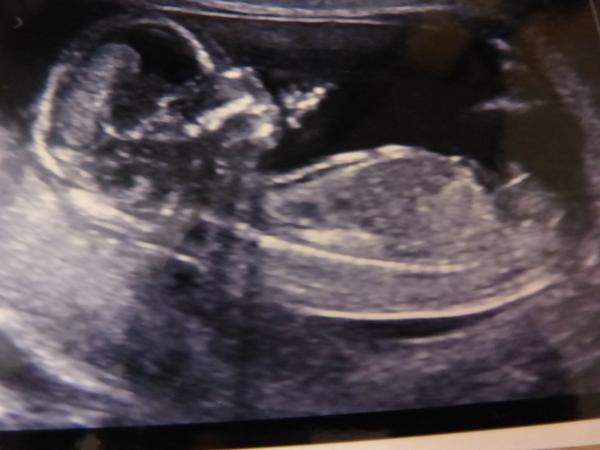

Tohle 26.tyden, ale krasne to bylo vidět už ve 20.tem 🙂

@misina01 ja už jsem sem davala taky slo.krasne videt uz kol toho 20tt jen mne zajimalo kolik je toto 🙂